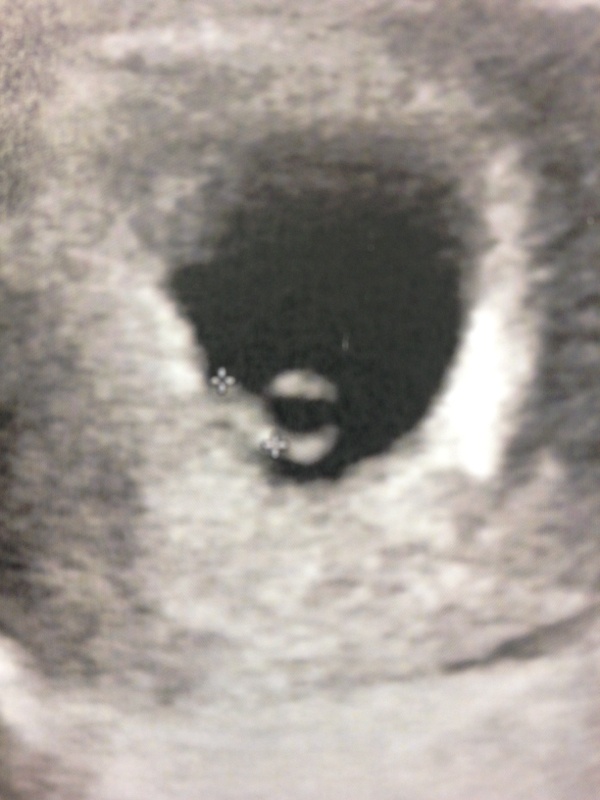

pour la datation je serai a 9sa. jespere qu'on va y voir quelque chose que meme lol

Je crois que j'etais a 6 semaines pour la datation et on a entendu le coeur

J'avais fais mon écho de datation à 8sa et pareil on a entendu le coeur et on a vu un petit haricot

Pour cette grossesse j'étais a 1 SA dc j'ai vu bb presque aussi bien qu'a l'écho des 3 mois! Pour Marley par contre je devais etre a 6/7sem et ca faisait comme Pauline on voyais une poche noire surtt lol